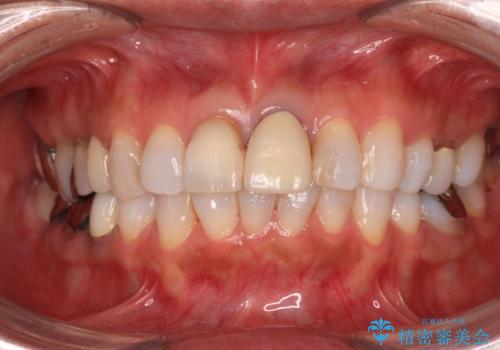

元々の歯の色が非常に白く、セラミッククラウンの色調を合わせるのに苦労しましたが、最終的に大変満足いただけるクラウンを装着することができました。